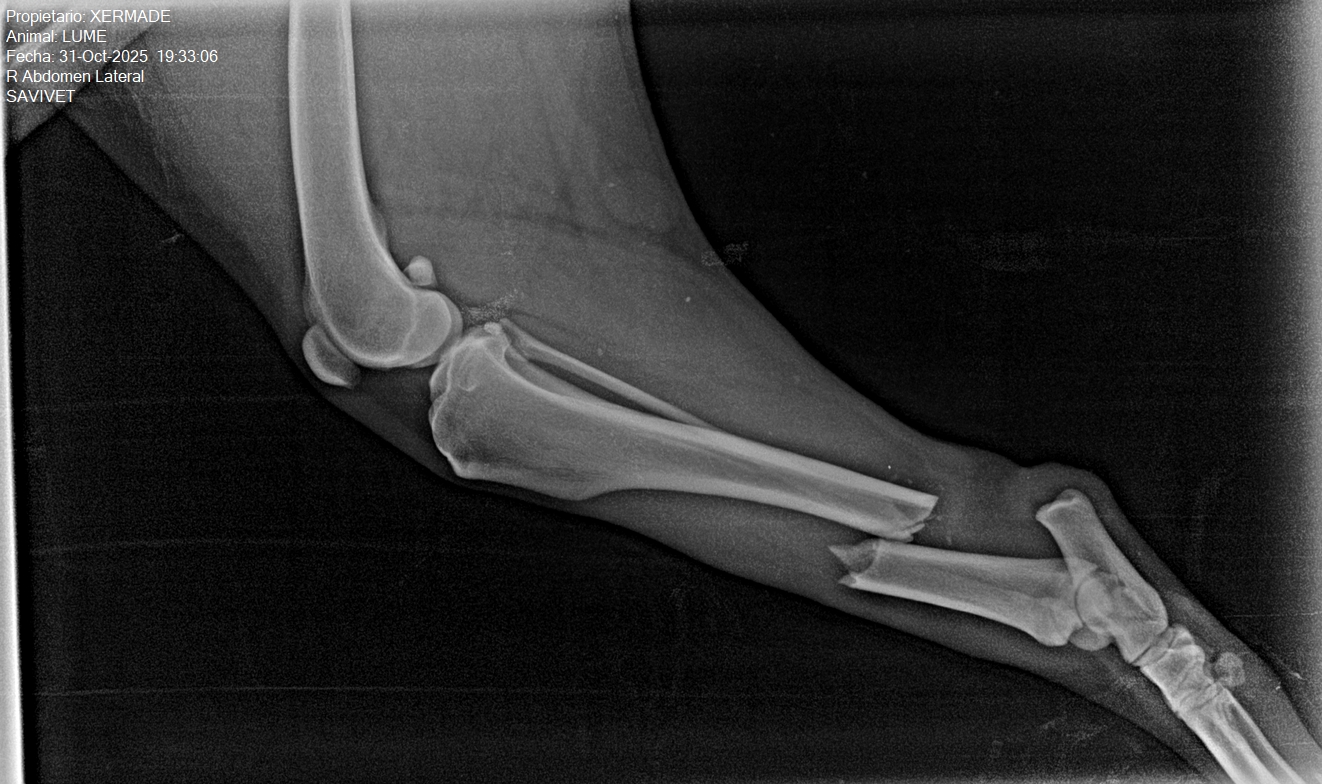

Immer wieder gibt es leider Sadisten auf der Welt. Valo ist ein trauriges Beispiel dafür. Diesem lieben, gutmütigen Hund wurden in einem Roma-Dorf in Bulgarien mit einem Messer beide Ohren abgeschnitten und dann wurde er im strömenden Dauerregen an einem kurzen Strick an einem Baum angebunden. Sein Körper war voller Blut und eiskalt. Tagelang saß er hilflos und mit wahnsinnigen Schmerzen angebunden dort schutzlos im Regen und in der Kälte. Katja vom Tierheim Dona dogs konnte ihn retten und der liebe Rüde hat den schönen Namen Valo bekommen, da er zwei Tage vor Valentinstag gerettet wurde. Nun befindet sich Valo in der Ottovet Tierklinik in Pazardzhik. Neben den Verletzungen an den Ohren hat Valo eine Lungenentzündung. Valo wird in der Klinik bleiben, bis er stabil ist. Lt. Klinikpersonal ist Valo ein Schatz, der alle Untersuchungen still über sich ergehen lässt, niemals knurrt oder schnappt, als wenn er weiß, dass ihm geholfen wird. Er ist ein sehr lieber und geduldiger Patient. Hunderettung-aktiv e. V. hat zunächst einmal 200,00 € als Spende für die Klinikkosten überwiesen. Wir werden weiter über Valo berichten und hoffen, dass es ihm bald besser gehen wird. Danke an Katja und ihr kleines Team vom Tierheim Dona dogs in Bulgarien und an Rali.